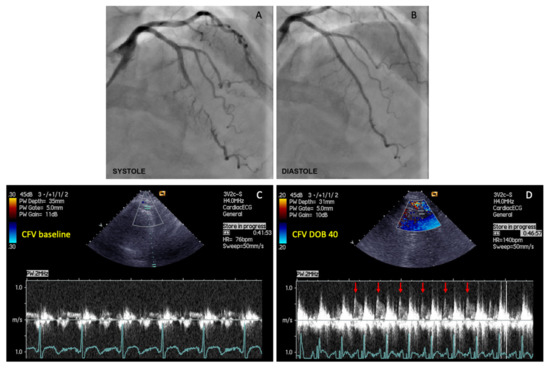

Maximal (peak) diastolic coronary flow velocities (CFVs) under basal conditions and during maximal hyperemia induced by peak dobutamine infusion (30 or 40 µg/kg/min) were measured in the distal segment of LAD, by a senior investigator who was blinded for the patient’s clinical and functional status (Figure 1). CFVR was calculated as the ratio between peak diastolic CFV obtained during peak dobutamine infusion and peak diastolic CFV under basal conditions.

Figure 1. The example of coronary flow velocity reserve (CFVR) measurements obtained by transthoracic Doppler echocardiography (TTDE) in the left anterior descending (LAD) artery distal to the myocardial bridging (MB), before and during iv. infusion of high-dose dobutamine (40 µg/kg/min). (A) Coronary angiography revealed myocardial bridging (MB) with severe intramyocardial LAD segment compression (>90% diameter stenosis) during systole; (B) Coronary angiography showed a significant decompression of intramyocardial LAD segment during diastole in the same patient; (C) CFV measurement under basal conditions (CFV baseline), and (D) CFV measurement at peak dobutamine dose (CFV DOB 40). The heart rate under basal conditions was 76 bpm, while during peak dobutamine infusion was 140 bpm (delta-HR 64 bpm). Coronary flow velocity reserve equals 2.96 (CFV DOB 40/CFV baseline = 0.77/0.26 = 2.96). Red arrows showing characteristic diastolic CFV profile during peak dobutamine infusion in the LAD distal to the MB. This phenomenon is characterized by an abrupt acceleration followed by rapid deceleration of the CFV at early-diastole and flow plateau during mid-to-late diastole (“finger-tip” phenomenon). CFV = coronary flow velocity; DOB 40 = dobutamine at 40 µg/kg/min.